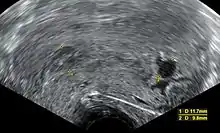

- الإجهاض غير الكامل:هو ان يبقى في الرحم جزء من الحمل .[39] زيادة المسافة بين جدران الرحم بواسطة تنظير المهبل وقد يزيد من سمك بطانة الرحم. يتم اكتشاف بقايا الحمل داخل الرحم بواسطة اشعة دوبلر [40] في حالة الحمل خارج الرحم يتم كشفه عن طريق فحص هرمون hcg [40]

معايير الأشعة فوق البنفسجية: اثبتت الدراسات في المجلة الطبية في انجلترا معتمدة على منظمة الاشعة والاشعة فوق البنفسجية في أمريكا. حيث حددت المعايير التي يثبت فيها الإجهاض.[37]

- يجب أن يكون طول الجنين على الاقل 7 ملم وبدون نبض [الإنجليزية]

- يجب ان يكون قطر كيس الحمل من 16 – 24 ملم وبدون بويضة مخصبة

- غياب النبض بعد 7-13 يوم بعد اخذ الاشعة فوق البنفسجية التي اظهرت كيس الحمل بدون بويضة مخصبة